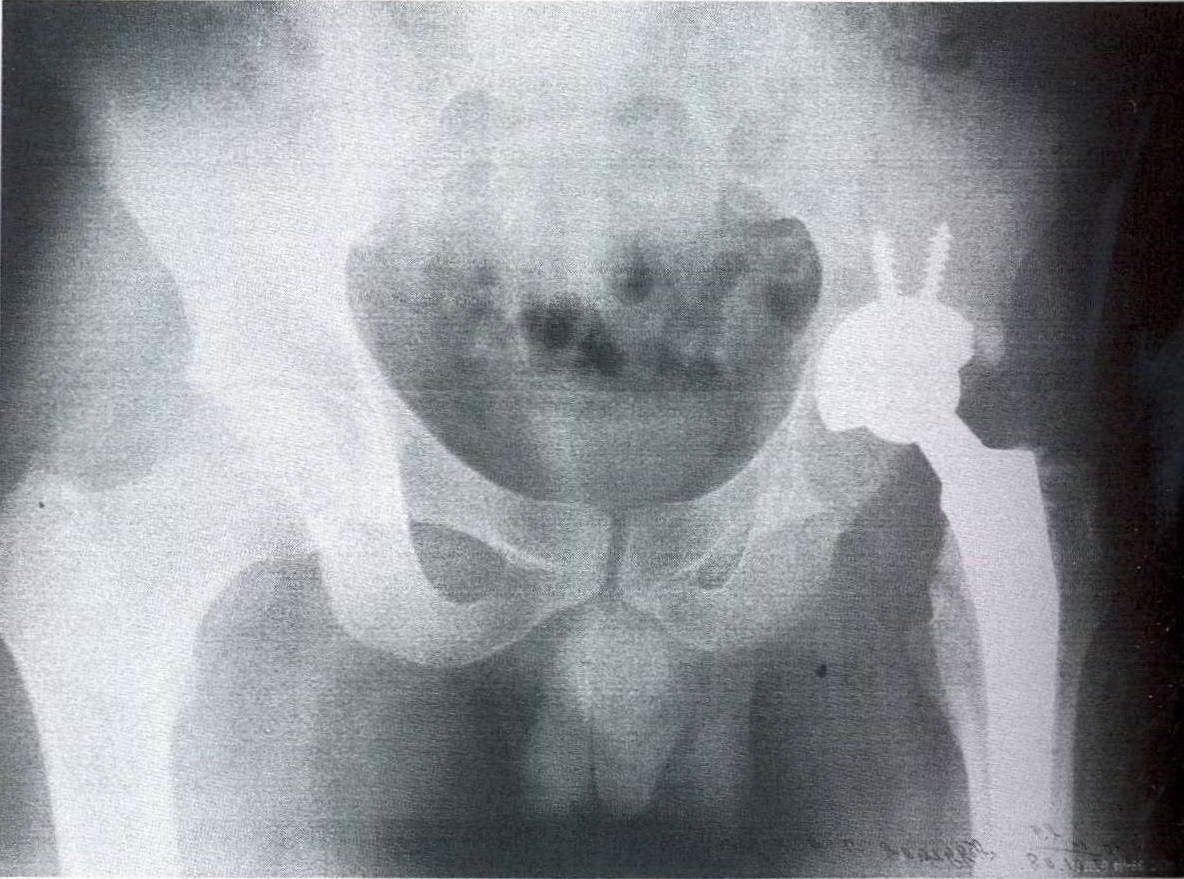

Рентгеновские снимки: Синовит тазобедренного сустава